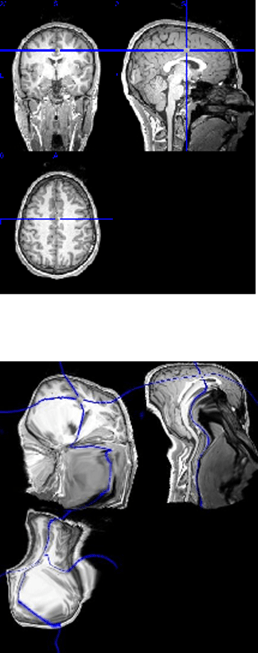

MoKa

Software to map the functional space of fMRI data with a nonlinear method from transportation theory — Monge-Kantorovich. This new method enables more accurate analysis of between subject brain activity analysis and will drastically improve any study involving populations with different brain structure (eg. ageing populations, brain injuries, degenerative brain disease, Alzheimer’s disease).

The software is currently under development, but free to use. All source code can be found on GitHub: https://github.com/convergencelab/MoKa